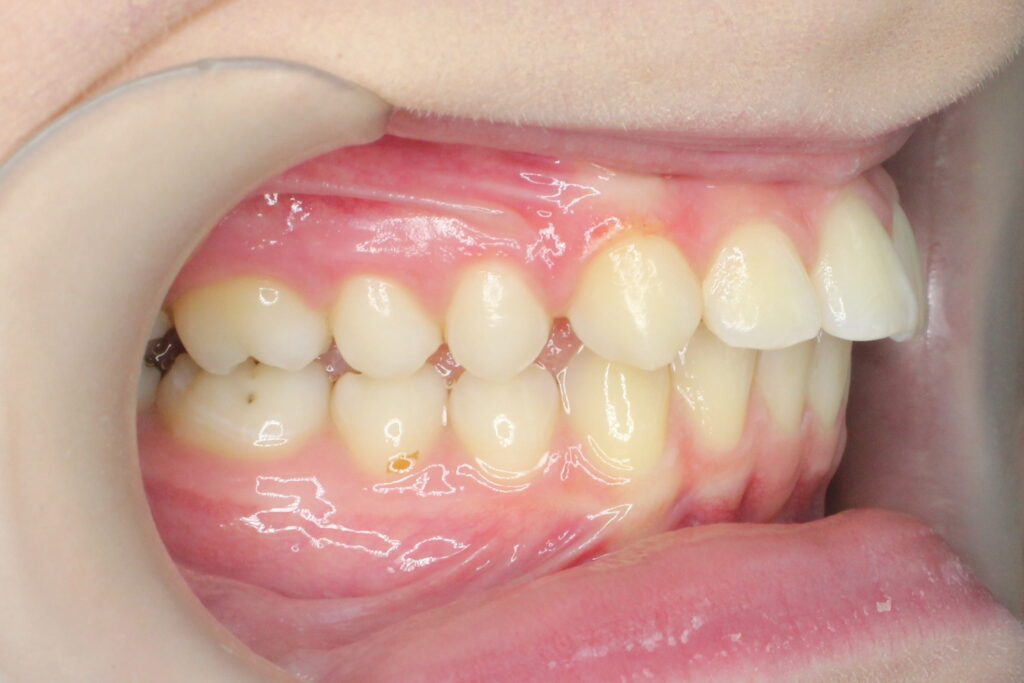

Ситуация до лечения

Диагноз: дистальный прикус, сужение, удлинение верхнего зубного ряда, скученность фронтальной группы зубов на нижней челюсти. Лечение проводилось самолигирующей брекет-системой Damon Q, срок лечения составил 2 года и 2 месяца.